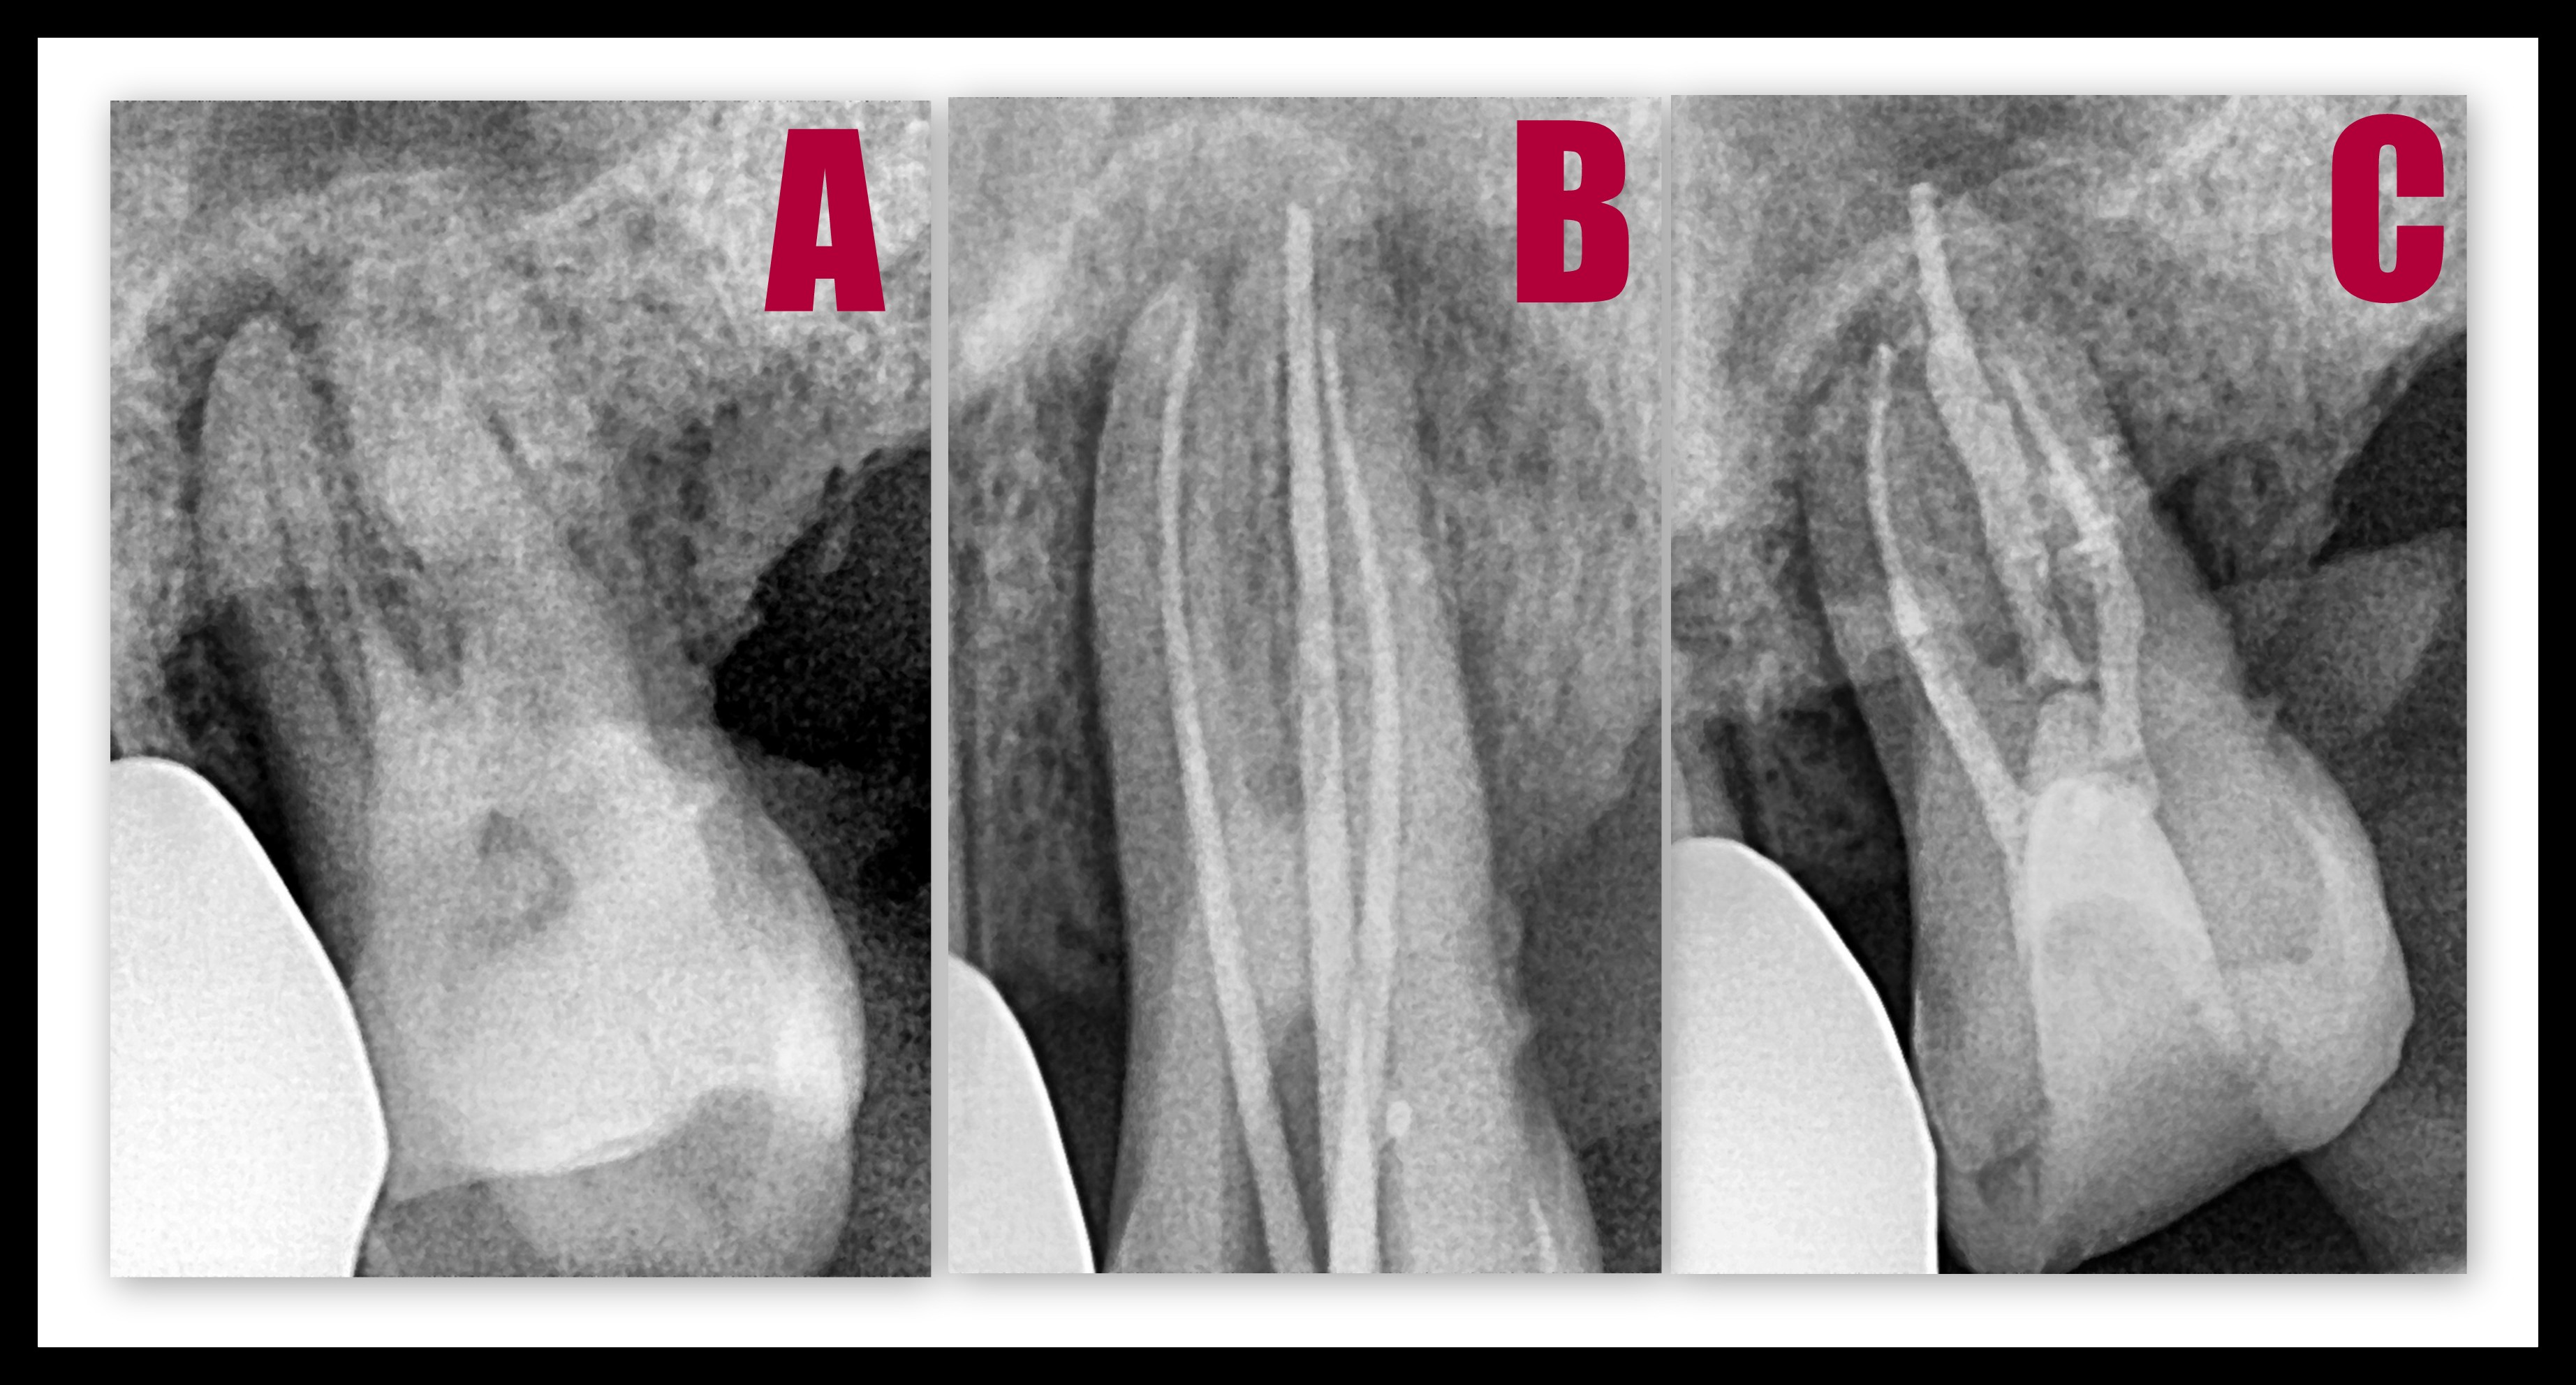

Root canal treatment is the removal of the infected soft tissue within the tooth and its replacement by an artificial inert ‘filling’ material. This procedure basically saves the tooth and eliminates dental pain.

ROOT CANAL TREATMENT